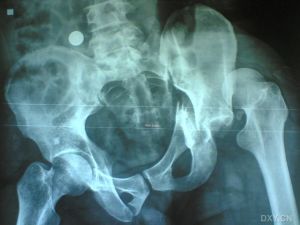

(1)I頭部x線檢查注意觀察有無骨折線通過腦膜中動脈和靜脈竇溝,一般可以幫助早期診斷。

(2)cT掃描不僅可以直接顯示血腫大小和部位,還可以了解腦室受壓和中線結構移位的程度及並存的腦挫裂傷、腦水腫等情況,應及早套用於疑有顱內血腫患者的檢查。硬腦膜外血腫cT表現為顱骨內板與硬腦膜之間的雙凸鏡形或弓形高密度影;急性或亞急性硬腦膜下血腫cT表現為腦表面新月形高密度、混雜密度影,多伴有腦挫裂傷和腦受壓;腦內血腫表現為腦挫裂傷區附近或腦深部白質內類圓形或不規則高密度影。